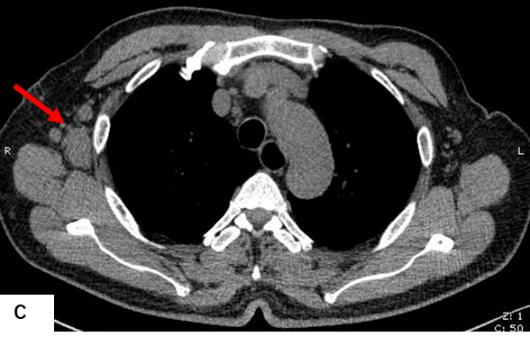

前列腺MRI示:前列腺移行帶結節狀異常信號,建議穿刺活檢;前列腺增生,PI-RADS2;雙側股骨頭信號異常,不排除轉移瘤(圖A)。為評估骨轉移情況遂行ECT全身骨顯像檢查,示:雙側肱骨頭、雙側股骨頭、右側前臂上段、右側股骨中下段代謝異常增強(圖B)。骨顯像不符合前列腺癌骨轉移典型表現,同時結合患者胸部CT(圖C)平掃示右側腋窩多發淋巴結腫大,生化檢查示乳酸脫氫酶620U/L(97-270),懷疑系血液系統腫瘤,建議患者行PET/CT檢查。PET/CT示:右側腦室內高密度灶,多發FDG代謝增高淋巴結及多發骨骼/骨髓FDG代謝增高灶,考慮淋巴瘤(圖D)。

胸部CT平掃示右側腋窩多發腫大淋巴結(紅箭)。